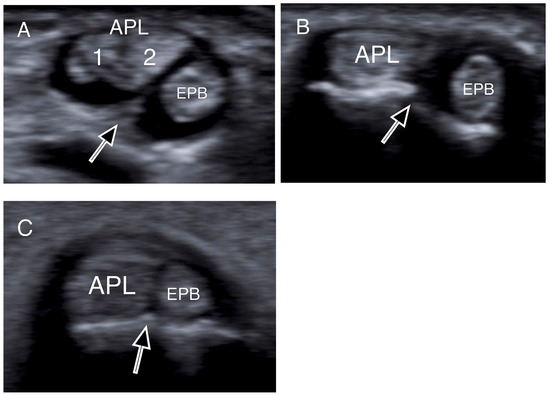

- Choi, S.J.; Ahn, J.H.; Lee, Y.J.; Ryu, D.S.; Lee, J.H.; Jung, S.M.; Park, M.S.; Lee, K.W. De Quervain Disease: US Identification of Anatomic Variations in the First Extensor Compartment with an Emphasis on Subcompartmentalization. Radiology 2011, 260, 480–486. [Google Scholar] [CrossRef]

- Kwon, B.C.; Choi, S.J.; Koh, S.H.; Shin, D.J.; Baek, G.H. Sonographic Identification of the Intracompartmental Septum in de Quervain’s Disease. Clin. Orthop. Relat. Res. 2010, 468, 2129–2134. [Google Scholar] [CrossRef]

| Intracompartmental septum | 27 (54%) |

| Double groove | 12 (24%) |

| 1 APL slip | 17 (34%) |

| 2 APL slips | 16 (32%) |

| 3 APL slips | 14 (28%) |

| 4 APL slips | 3 (6%) |